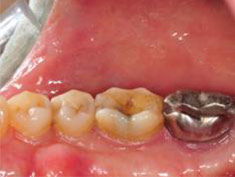

牙周初診時患者之口內觀。口內明顯牙菌斑及牙結石堆積。全口嚴重牙齦紅腫。治療前X光片。#37的近心側有較深的骨內缺損,剩餘齒槽骨高度只有20%。

第一階段牙周基本治療後,牙齦發炎狀況明顯獲得改善。

術後一年之全口X光片, #37近心側可見明顯骨充填與放射線密度增加。 牙周再生手術完成一年後追蹤,全口牙齦發炎狀況改善,牙周組織呈現健康狀況。#37金屬燒附陶瓷牙冠製作完成。